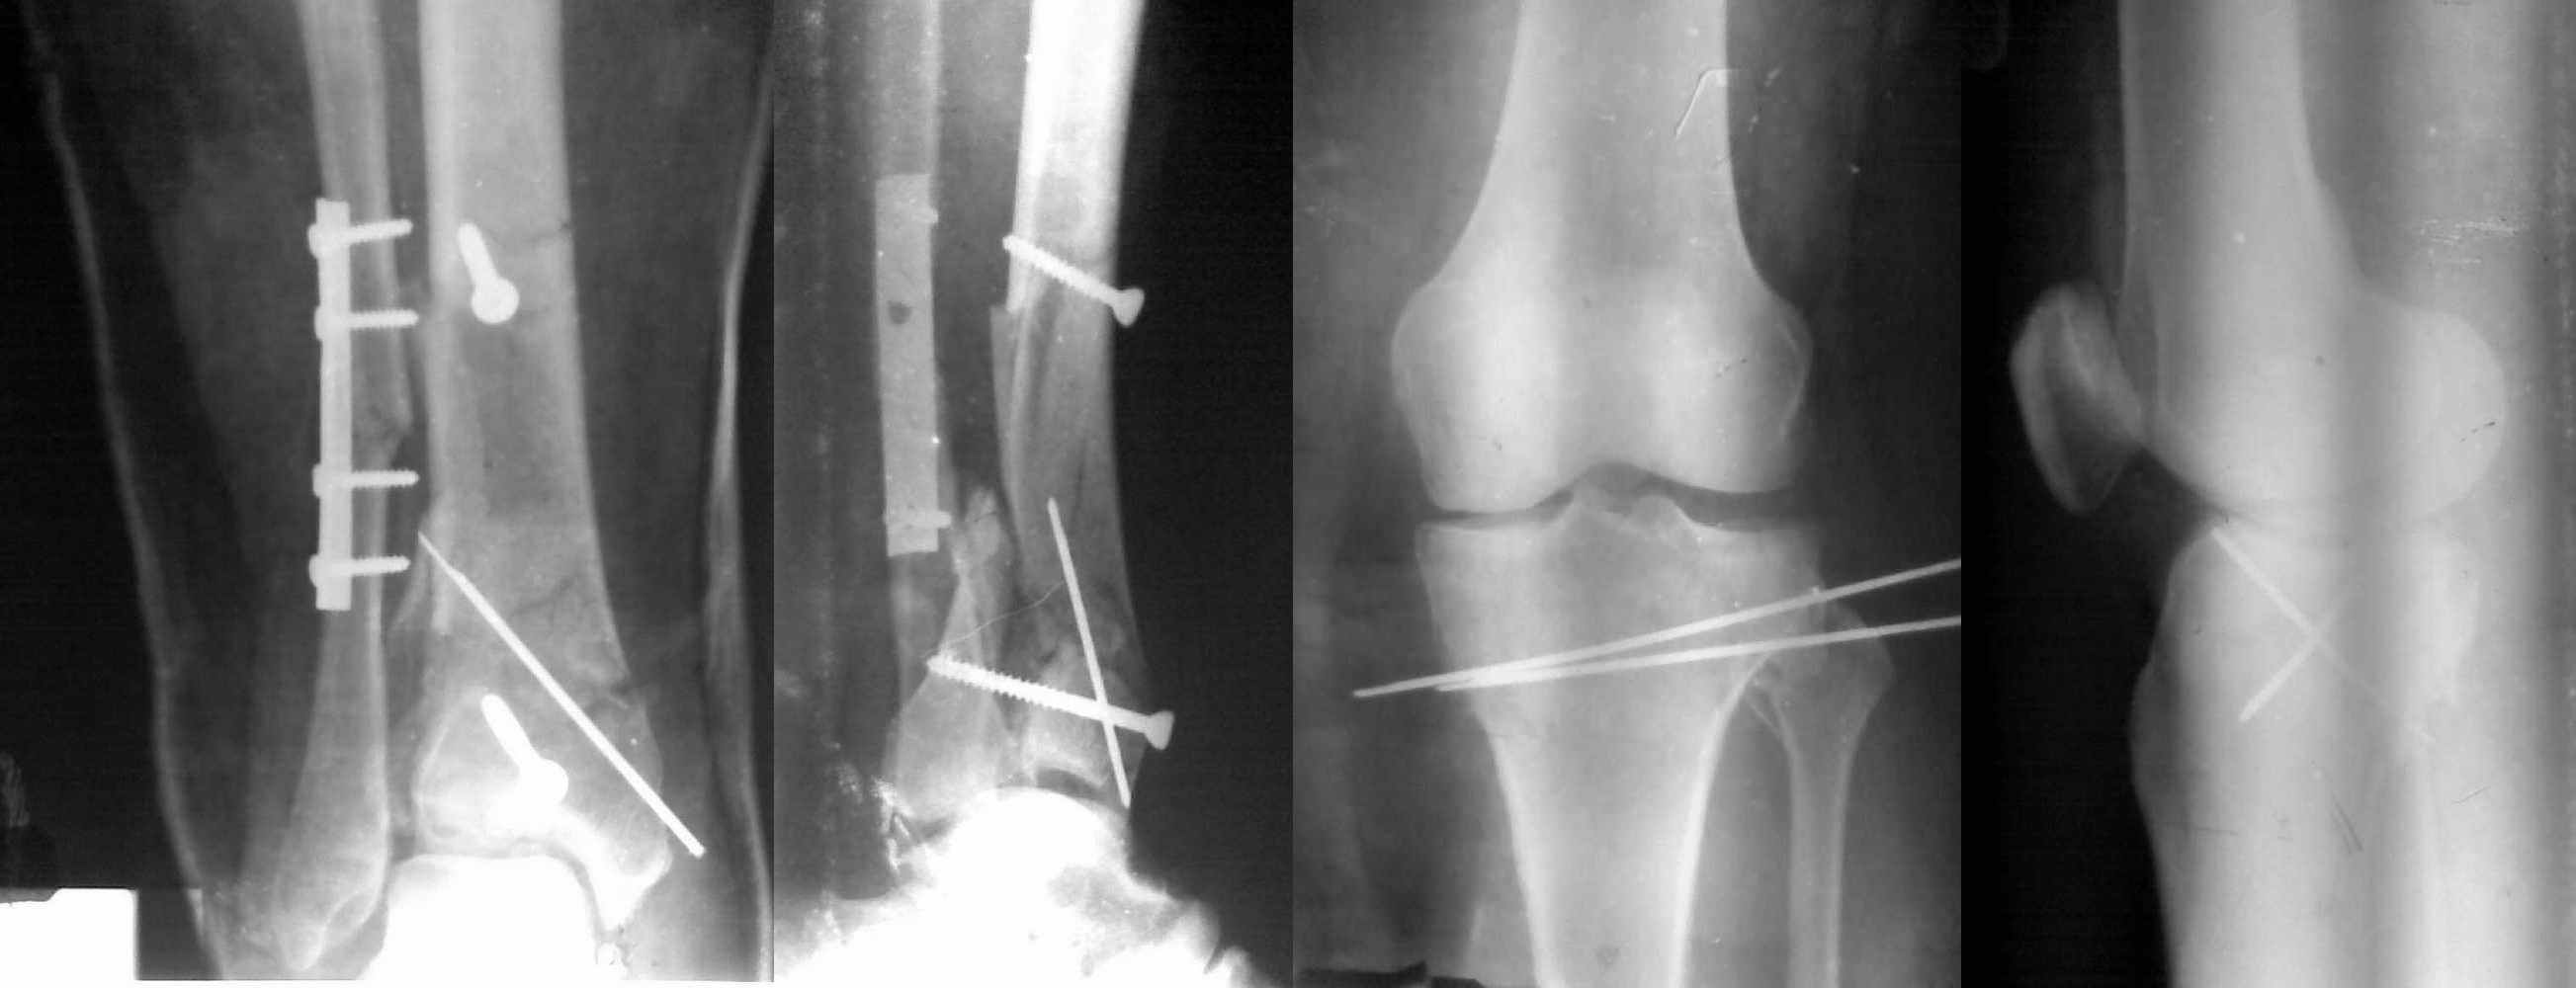

Снимки до и после закрытой репозиции

Пациентки прооперирована, результат чего на снимках. Выполнена открытая репозиция костей правой голени, синтез малоберцевой пластиной, б/берцевой винтами, имеющиеся фиксаторы не подходили, было принято решение репонировать отломки, синтез винтами, гипсовая повязка.

В данный момент локально отёк тыла стопы незначительный, двигательня функция сохранена, ограничена болевым синдромом. Пульсация артерий ослаблена, соответствует левой ноге. Рана - в области границы с пузырём область некроза 2.5*2 см, сухой, не увеличивается, под ним чувствительность сохранена. Чувствительность по всей поверхности кожи в норме, гипоестезия пальцев, при чём варьирует от нормальной, до почти анестезии в течении дня.

Мыщелок левой б/б кости репонирован закрыто, на контрольной рентгенограмме репозиция удовлетворительная, фиксировано спицами. гипсовая повязка.

Репозиция внутрисуставных переломов неудовлетворительная и не адекватна.

В лечении переломов пилона восстановление длины малоберцовой является индикатором и ориентиром для успешного лечения. Первый этап восстановления по длине не удался, малоберцовая остается короткой, и репозиция суставной поверхности осталась неудовлетворительной. Длина передней колонны не восстановлена, а в дистальном фрагменте имеется флексия. Оставлена без внимания потеря кости в метафизе. Шурупы 4.5 мм будут выступать после спадения отека, и возможно будут причиной мягкотканого осложнения в гипсе.